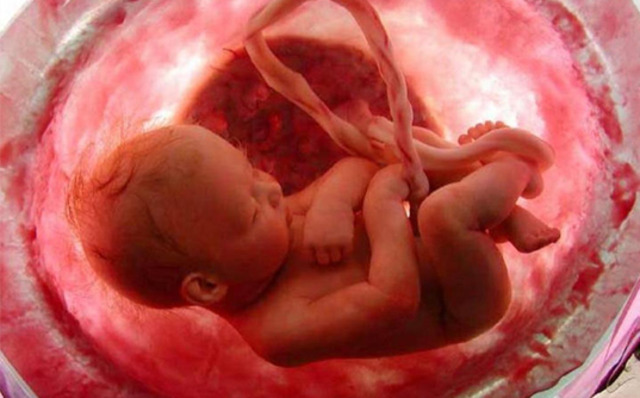

• Desenvolvimento das características masculinas

Desenvolvimento das características masculinas

Nessa fase, se o embrião tiver cromossomo Y, o gene SRY fará a produção do Fator Determinante de Testículo. As células germinativas primordais penetram profundamente no mesoderma gonadal, que se organiza em cordões testiculares e então em túbulos semíniferos. Diferenciam-se também as células de Sertoli, que secretam hormônio Anti-mulleriano -promove involução do ducto de Muller -, e células de Leydig, que secretarão testosterona - orientam evolução do ducto de Wolff no ducto deferente.

• Desenvolvimento das características femininas

Com a ausência da testosterona e a presença do estrogênio proveniente da placenta, os cordões gonadais se desorganizam, e as células primordiais migram para a periferia, formando o ovário. O ducto de Wolff não se desenvolve e o ducto de Müller progride formando as tubas uterias e o corpo do útero.

Desenvolvimento da Genitália Externa

A genitália, ainda indiferenciada nesse ponto, é formado por um tubérculo genital, pregas uretrais e uma prega anal. Nos homens, os andrógenos determinam a elongação do tubérculo, formando o falo, e o fechamento do sulco uretral, originando a uretra peniana. O estrogênio, nas mulheres, faz do tubérculo o clitóris e da prega uretral os lábios menores.